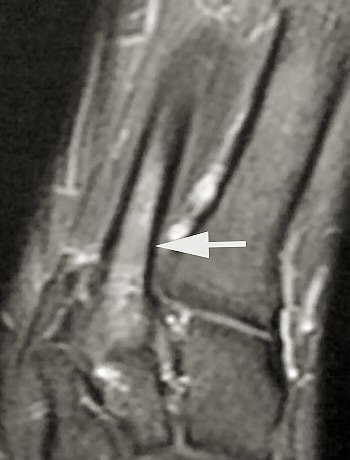

| MRI shows bone marrow edema at the base of the fifth metatarsal. All images courtesy of Duke University Medical Center, Durham, NC. |

The follow-up study was led by Dr. Nancy Major, associate professor of radiology at Duke University Medical Center's musculoskeletal division. Her study determined that MRI can effectively predict metatarsal stress fractures by depicting bone marrow edema (a precursor to fractures), thereby enabling the prevention of potential fractures with the use of orthotics.

In this study, 26 male basketball players from Duke and North Carolina Central University in Durham were imaged before and after their 2003 season. Although 19 of 52 feet showed abnormalities with MRI, only one player had complaints of a symptomatic midfoot. The use of an orthotic provided immediate relief, and the player did not subsequently develop stress fractures.